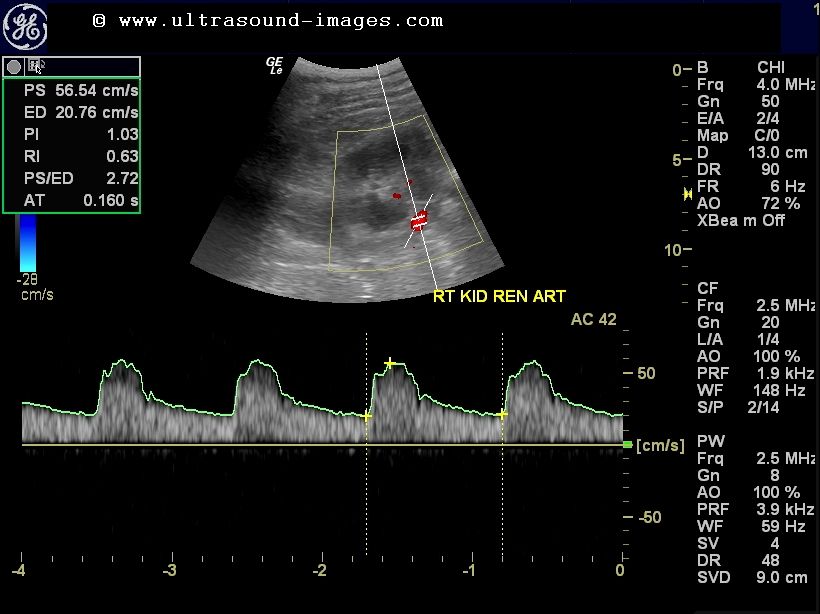

Spectral Doppler waveforms in the interlobar arteries right kidney Interlobar Artery Kidney Ultrasound Renal artery stenosis (ras) (plural: The present clinical practice recommendations are addressed to physicians of all specialties, who perform doppler ultrasound. When the process occurs slowly, it leads to. Describe classic imaging findings associated with renal artery stenosis, renal artery thrombosis, renal vein thrombosis, and pseudoaneurysms/arteriovenous. The case includes images, measurements, waveforms,. Find out the anatomy, technique, parameters, waveforms and. Interlobar Artery Kidney Ultrasound.